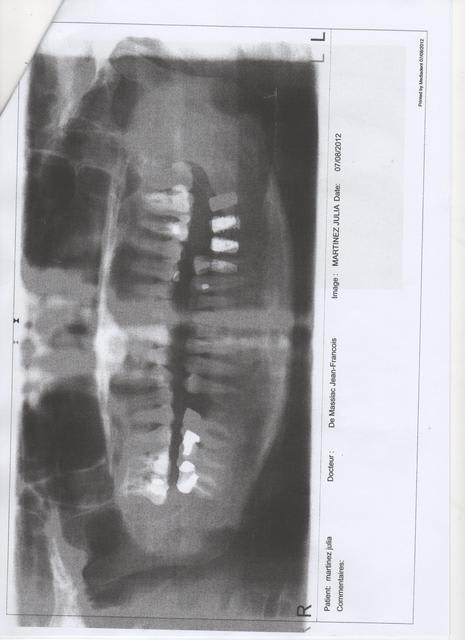

dhaibi

09/12/2012 à 12h10

Bjr

Messieurs les specialistes

suite poseur disparu

qu elles protheses sur ce genre d implants non identifiés?

Peut etre made in USA.

Tres cordialement

Panoramique julia kcxbmd - Eugenol